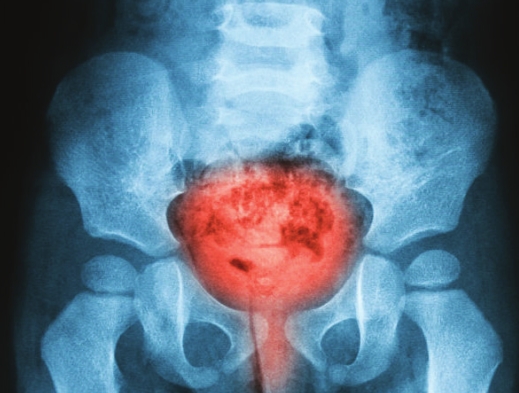

stimulation).Kidney StonesKidney stones tend to develop in midlife. They

form in the kidney itself and typically begin to cause the tell-tale

symptoms once they “move”or block the flow of urine from that kidney.

This is often very

painful. The size, location and degree of blockage will determine

whether the stone will likely pass on its own or require surgical

removal. As people from the South, the best thing we can do to prevent

stones is stay very well hydrated! We should also be mindful of our salt

(sodium) intake, as too much sodium can increase the risk of formation

of new stones. Lastly, adding citrate-rich fruits and vegetables can

decrease the risk of stones.